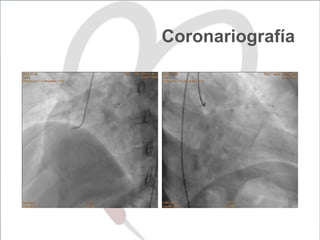

Coronariografía

ICP con DES en coronaria

derecha y descendente anterior

DES	3.0/48	@	16	atm	 DES	3.5/18	@	16	atm